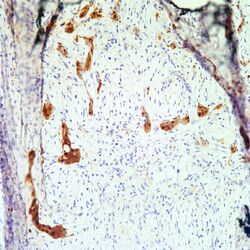

Aug 15, 2021 · mesothelioma treatments are available, but for many people with mesothelioma, a cure isn't possible. What kind of cells are found in malignant mesothelioma? Free guide overnighted · treatment options · financial assistance What are the markers of malignant pleural mesothelioma? Malignant tumor that develops from mesothelial cells. Our free guide includes information on legal compensation, treatment options, and more. Mesothelioma is a malignancy involving mesothelial cells that line the body cavities, including the pleura, peritoneum, pericardium, and testis; Which is high risk for malignant mesothelioma in situ? Mesothelioma can occur at any mesothelial layer such as the peritoneum or pericardium. Tanner marshall, ms, yifan xiao, md, vincent waldman, phd mesothelioma is an aggressive cancer that attacks the mesothelium, which is a thin membrane made of epithelial cells that lines all of the body's organs as well as body spaces like the thoracic cavity and abdominal cavity. Jul 10, 2021 · malignant mesothelioma is a rare growth of mesothelial cells strongly associated with asbestos exposure. Epidemiology incidence ~3,000 cases diagnosed/year in the us; Jul 21, 2021 · mesothelioma usmle.

Required fields are marked * save my name, email, and website in. Which is high risk for malignant mesothelioma in situ? Your email address will not be published. We'll deliver the guide overnight and free of charge. What are the markers of malignant pleural mesothelioma? Our mesothelioma course covers all essentials: Less commonly the lining of the abdomen and rarely the sac surrounding the heart, or the sac surrounding the testis may be affected. Jul 21, 2021 · mesothelioma usmle. What kind of treatment do you get for mesothelioma? Aug 15, 2021 · mesothelioma treatments are available, but for many people with mesothelioma, a cure isn't possible. Free guide overnighted · treatment options · financial assistance Epidemiology incidence ~3,000 cases diagnosed/year in the us; Mesotheliomas represent a proliferative neoplasm made up of epithelial and mesenchymal cells of the mesothelium which make up part of the serosal covering and lining of various organ surfaces within the body.

Mesotheliomas represent a proliferative neoplasm made up of epithelial and mesenchymal cells of the mesothelium which make up part of the serosal covering and lining of various organ surfaces within the body. Malignant tumor that develops from mesothelial cells. What are the markers of malignant pleural mesothelioma? Leave a reply cancel reply. Our mesothelioma course covers all essentials: We'll deliver the guide overnight and free of charge. Our free guide includes information on legal compensation, treatment options, and more. Mesothelial cells form the lining layers of the viscera.